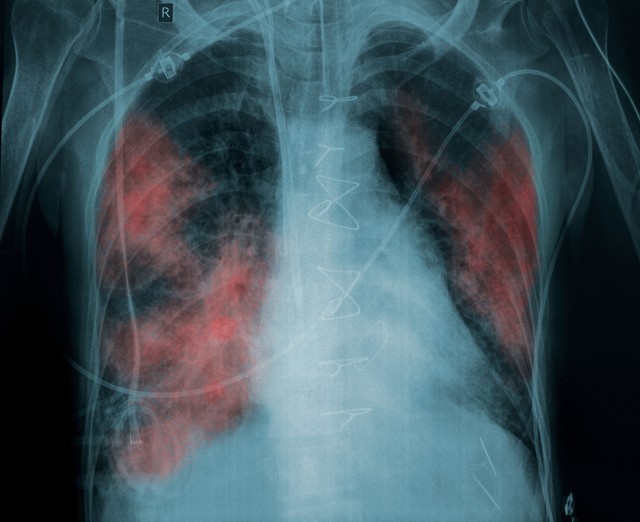

Európai összehasonlításban is kiemelkedő a HIV-ellátás színvonala, azonban még mindig magas a későn kiszűrt betegek aránya, és alacsony a szűrési hajlandóság – mutattak rá a Pro Infectologia Alapítvány szakértői a Dél-pesti Centrumkórházban az AIDS-világnap alkalmából tartott hétfői sajtótájékoztatón.